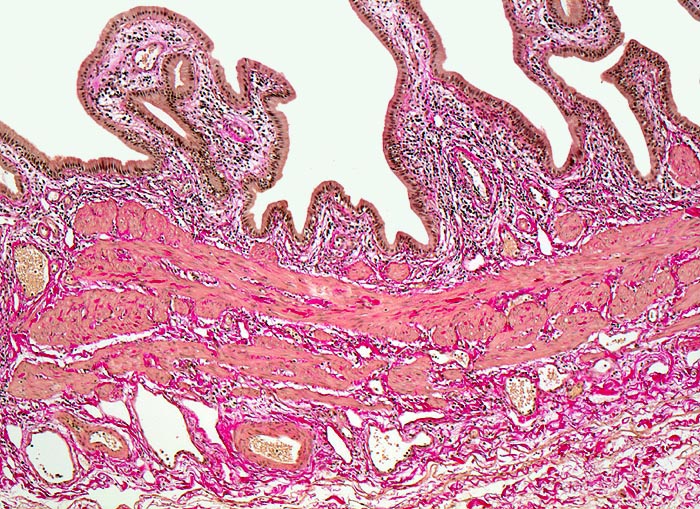

Normale Gallenblase

Normalbefund

Gallenblase

Leber, Gallenwege, Pankreas

Die Gallenblasenschleimhaut bildet unregelmässige

Falten, die bedeckt sind von einem

hochzylindrischen Epithel. Auf die Mukosa folgt eine Schicht mit

glatter Muskulatur. Am unteren Bildrand das Bindegewebe der

subserösen Schicht.

Histologie

50